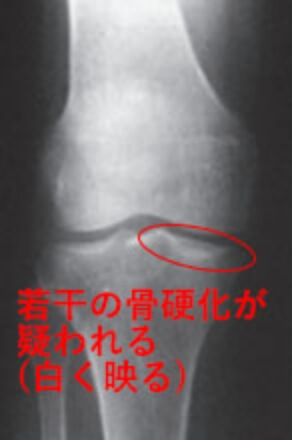

1 変形性膝関節症が疑われる状態。

関節裂隙狭小化※1は無。骨棘※2や骨硬化※3が見られることがある。

K-L分類Grade1のX線画像